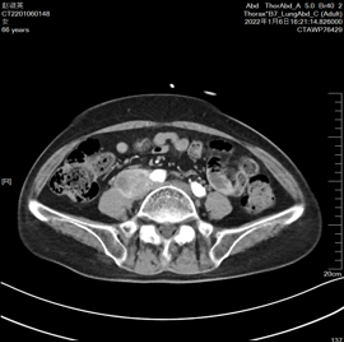

2022-04-12

2022-07-21(SD)

2022-12 CT提示病情缓慢进展,疗效评价SD。继续:特瑞普利单抗。

2022-12(病情缓慢进展)